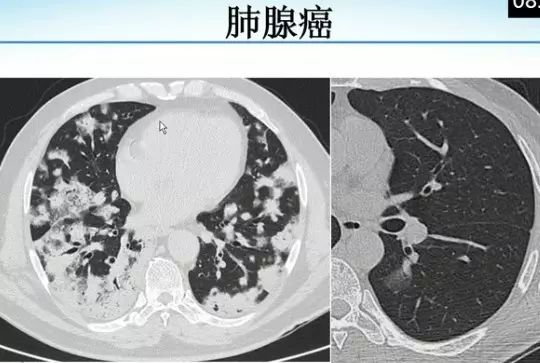

肺内“烟花征”,为活动性肺结核的CT表现之一。是结核经支气管播散并由多发小叶中央结节堆积而成,形态特征似烟花在空中散开。病理基础为细支气管及肺泡内干酪坏死性肉芽肿。

下文为解放军总医院放射诊断科赵绍宏教授课件分享,希望同行朋友们下次遇到类似病例,能够正确诊断。再次感谢赵教授的精彩讲解。